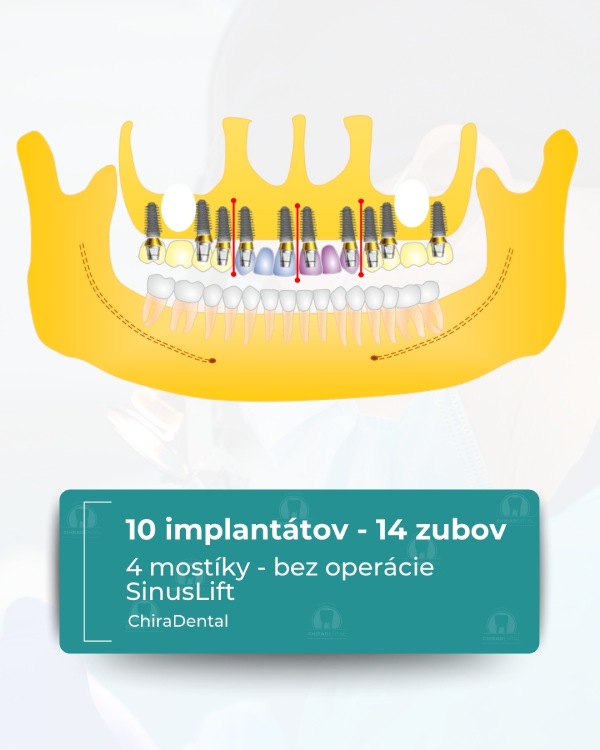

⭐ Možnosť 3 — Prémiové (10 implantátov)

Najspoľahlivejšia a najkomplexnejšia rehabilitácia, ktorá zabezpečuje vynikajúcu pevnosť a trvanlivosť.

V cene:

Inštalácia 10 implantátov so súčasnou augmentáciou kosti a korekciou mäkkých tkanív;

Odtlačky pre dočasnú rekonštrukciu sa robia nasledujúci deň;

Dočasné zuby sa fixujú za 3-5 dní.

Výsledok: 14 dokonale rozmiestnených zubov. Konečná rekonštrukcia po 3-6 mesiacoch: — kovovo-keramická alebo zirkónová, — konštrukcia je rozdelená na 3 mostíkové segmenty (centrálny + dva bočné), čo zaisťuje dokonalú stabilitu a jednoduchú údržbu.